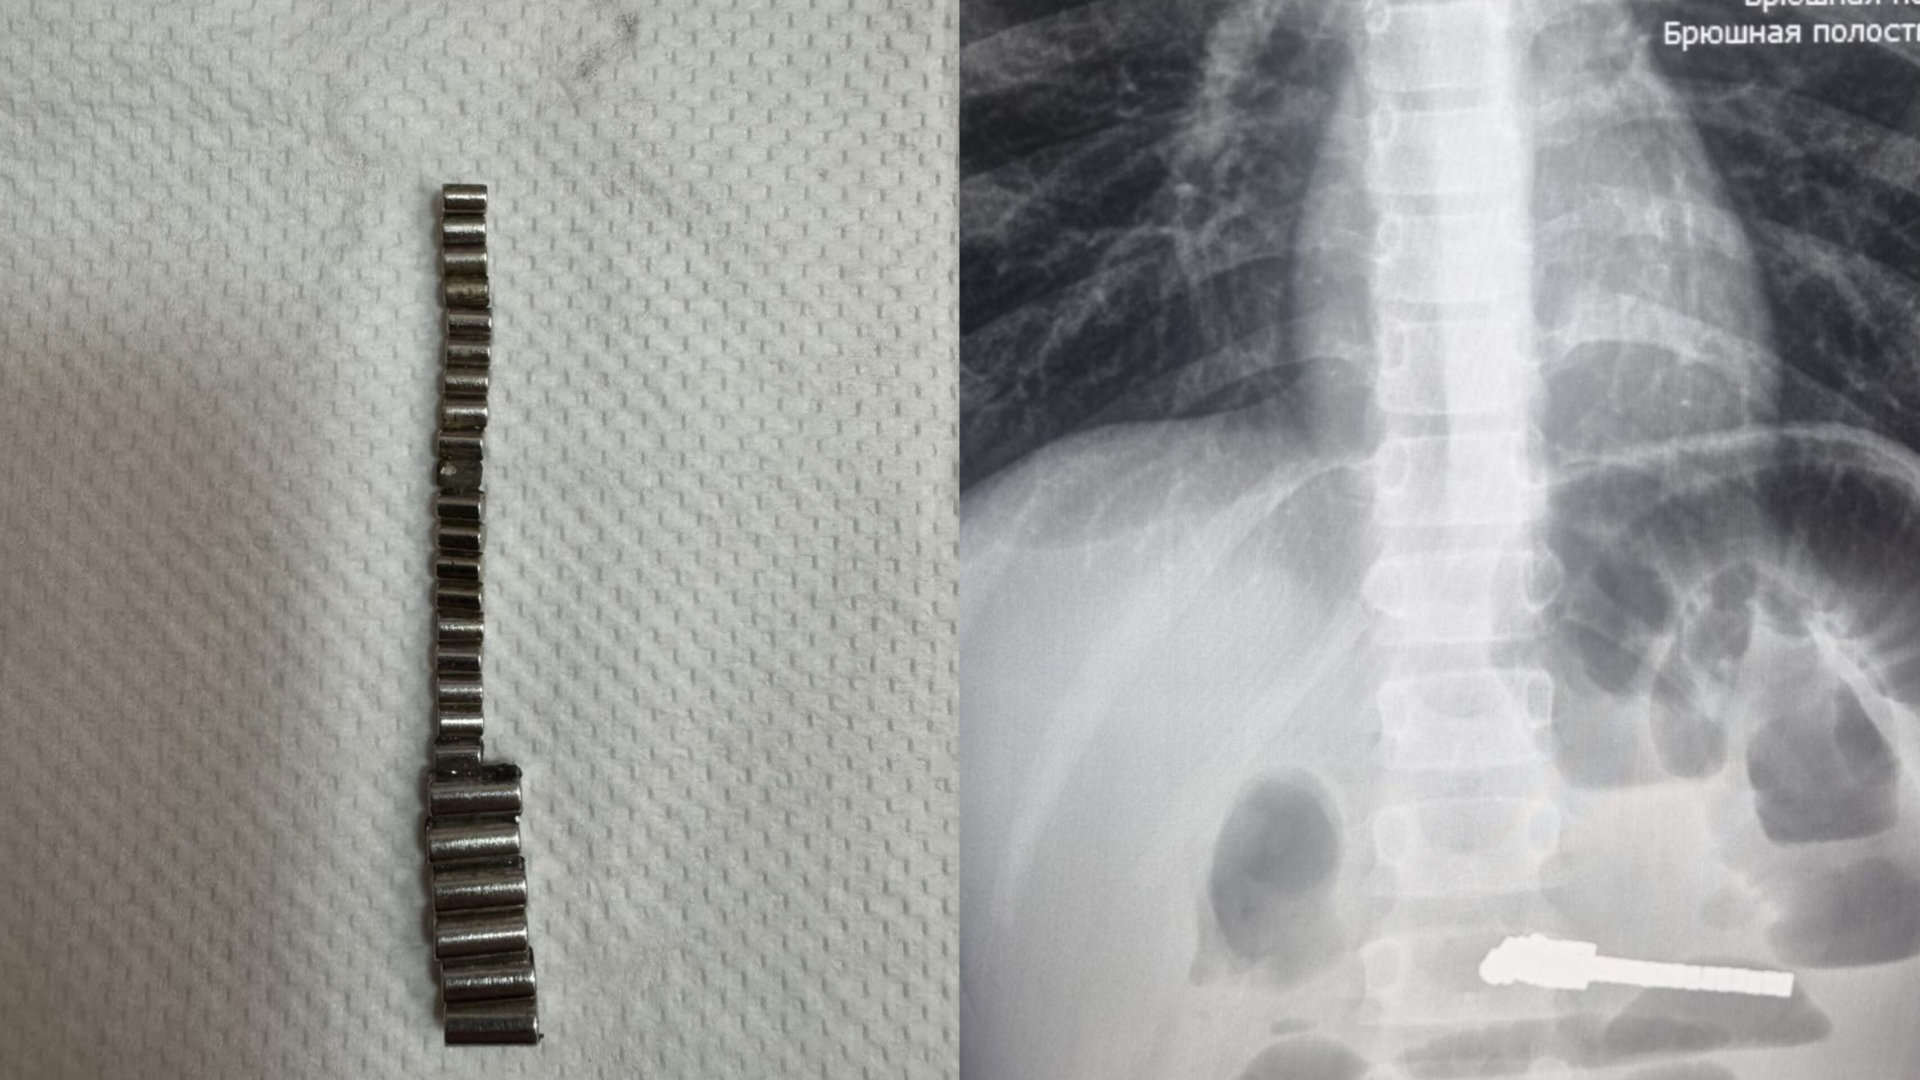

В приёмное отделение Детской городской клинической больницы № 1 города Новосибирска поступил юный пациент с жалобами на рвоту и сильные боли в животе. Причину установили, когда сделали рентген брюшной полости. Историей поделилась пресс-служба Минздрава Новосибирской области.

Оказалось, что в кишечнике ребёнка находились инородные предметы. Врачи больницы провели оперативное хирургическое вмешательство и извлекли из желудка пациента 25 магнитов. Длительное нахождение подобных предметов в ЖКТ привело к серьёзным осложнениям, но, к счастью, сейчас жизни ребёнка ничего не угрожает. Операция прошла успешно.